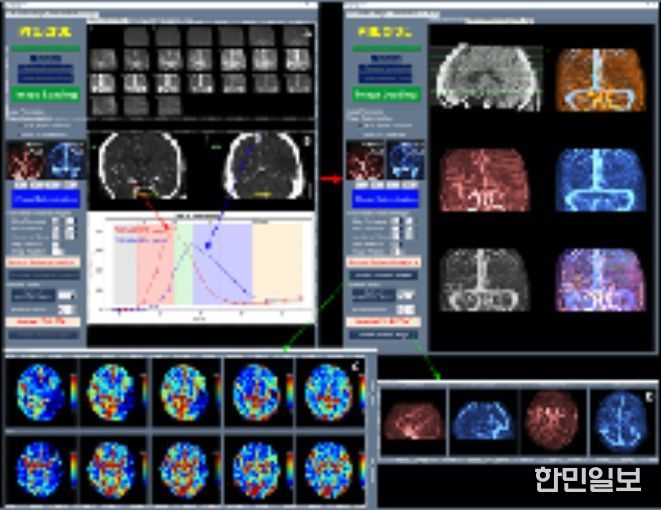

이와 함께 허혈성 뇌혈관 질환 환자를 대상으로 혈관재개통 치료가 필요한 환자 선별을 지원하는 소프트웨어 등 다양한 진단·치료 보조 AI 의료기기들이 혁신의료기기로 지정됐다.